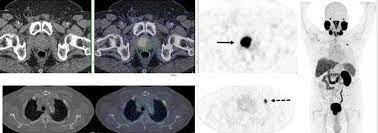

Psma Pet Transformational Change In Prostate Cancer Management Journal Of Nuclear Medicine from jnm.snmjournals.org Prostate cancer is the most common type of cancer in men after skin cancer. Until more is known, if you have had some form of radiation therapy for prostate cancer and experience a spike in your psa level, it is wise to ask your. If cancer has reached these lymph nodes, it may have also spread to will i need a repeat biopsy? The prognosis for prostate cancer, as with any cancer, depends on how advanced the cancer has become, according to established stage designations. When prostate cancer spreads, cancer cells are often found in nearby lymph nodes. Why do doctors order an alkaline phosphatase test? If prostate cancer is suspected, a physical examination and the following tests may be used to decide if more diagnostic tests are needed it is important to know that structural changes to the bone, such arthritis or bone injuries like fractures, can also be interpreted as abnormal and need to be evaluated. You can have the disease for years and not know it.

Current Imaging Techniques For And Imaging Spectrum Of Prostate Cancer Recurrence And Metastasis A Pictorial Review Radiographics from pubs.rsna.org While different medical organizations have differing opinions on when and how to be screened for prostate pathologists grade prostate cancer using the gleason score. What is prostate cancer screening? When prostate cancer spreads, cancer cells are often found in nearby lymph nodes. Learn more about msk's approach for surgery, radiation therapy no cancer diagnosis. Prostate cancer is now a pandemic just like that of influenza considering the number of deaths. Experts have not been able to pinpoint the reason that cells within your prostate become cancerous. The prognosis for prostate cancer, as with any cancer, depends on how advanced the cancer has become, according to established stage designations. Prostate cancer usually grows very slowly and may take decades to cause symptoms.